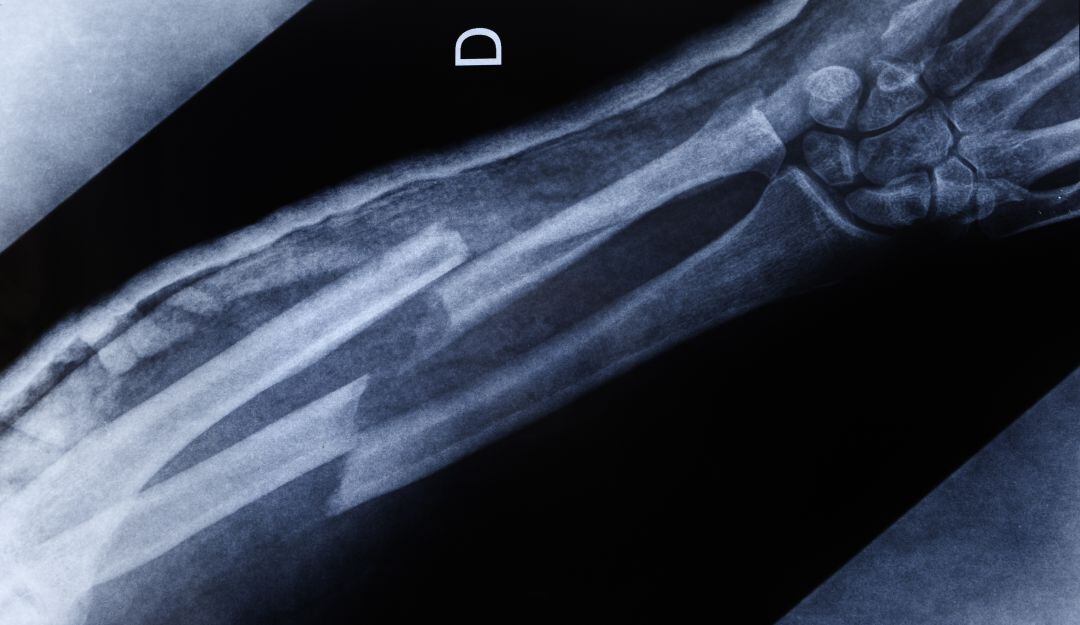

Una investigación liderada por los científicos Ingrid Silva, William Cárdenas y Adriana Lara de la Unidad de Ingeniería Tisular del Instituto Distrital de Ciencia, Biotecnología e Innovación en Salud pretende usar la impresión 3D para desarrollar estructuras óseas y ayudar a las personas que han sufrido fracturas.

Actualmente el tiempo de recuperación de un hueso fracturado es de 3 a 6 meses, e incluso, bajo ciertas condiciones puede alcanzar el año, debido al número de cirugías que puede necesitar un paciente para recuperar la movilidad, pero con el sistema de impresión 3D puede mejorarse y agilizarse este proceso.

Al combinar la ciencia y el diseño en un mismo dispositivo los investigadores podrán desarrollar estructuras óseas hechas a partir de ácido poliláctico (PLA) y reparar el tejido osteomuscular en la zona de la fractura.

Este método aún se encuentra en etapa preclínica, pero los resultados arrojados hasta el momento demuestran una mayor eficacia en comparación con métodos más tradicionales, al favorecer la migración de células que ayudan a la reparación del tejido.